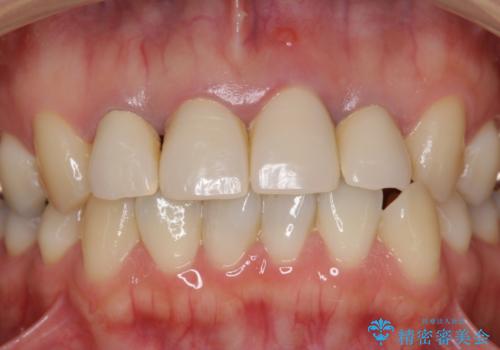

黒っぽい歯ぐきを改善したい メタルフリーセラミック治療

- 歯ぐきの黒っぽさ、暗い色調の前歯の改善を求めて来院されました。

金属を用いたコア・クラウンが装着されており、全ての金属を除去したのちのメタルフリー治療を計画します。

金属のフレームを用いるクラウンは色調が暗くなる傾向にありますが、セラミッククラウンに置き換えたことで自然な明るさ、審美性を取り戻すことができました。